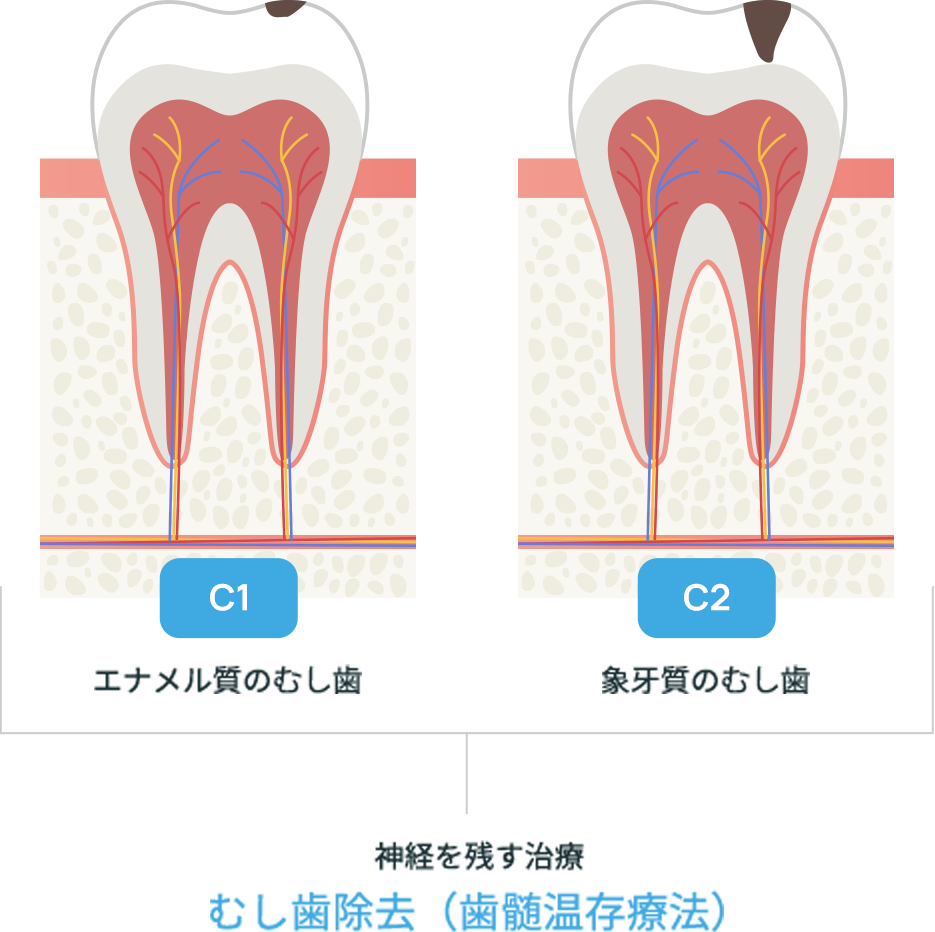

進行度によって変わるアプローチ

むし歯は進行度によって治療方法が変わってきます。状態を見極めて治療を選択します。

むし歯治療

(歯髄温存療法:覆髄、断髄)

神経を残してむし歯の感染部分を取り残さないように取り除くことで治療します。健康な歯をできるだけ残せるように、拡大鏡を使用して治療を行います。